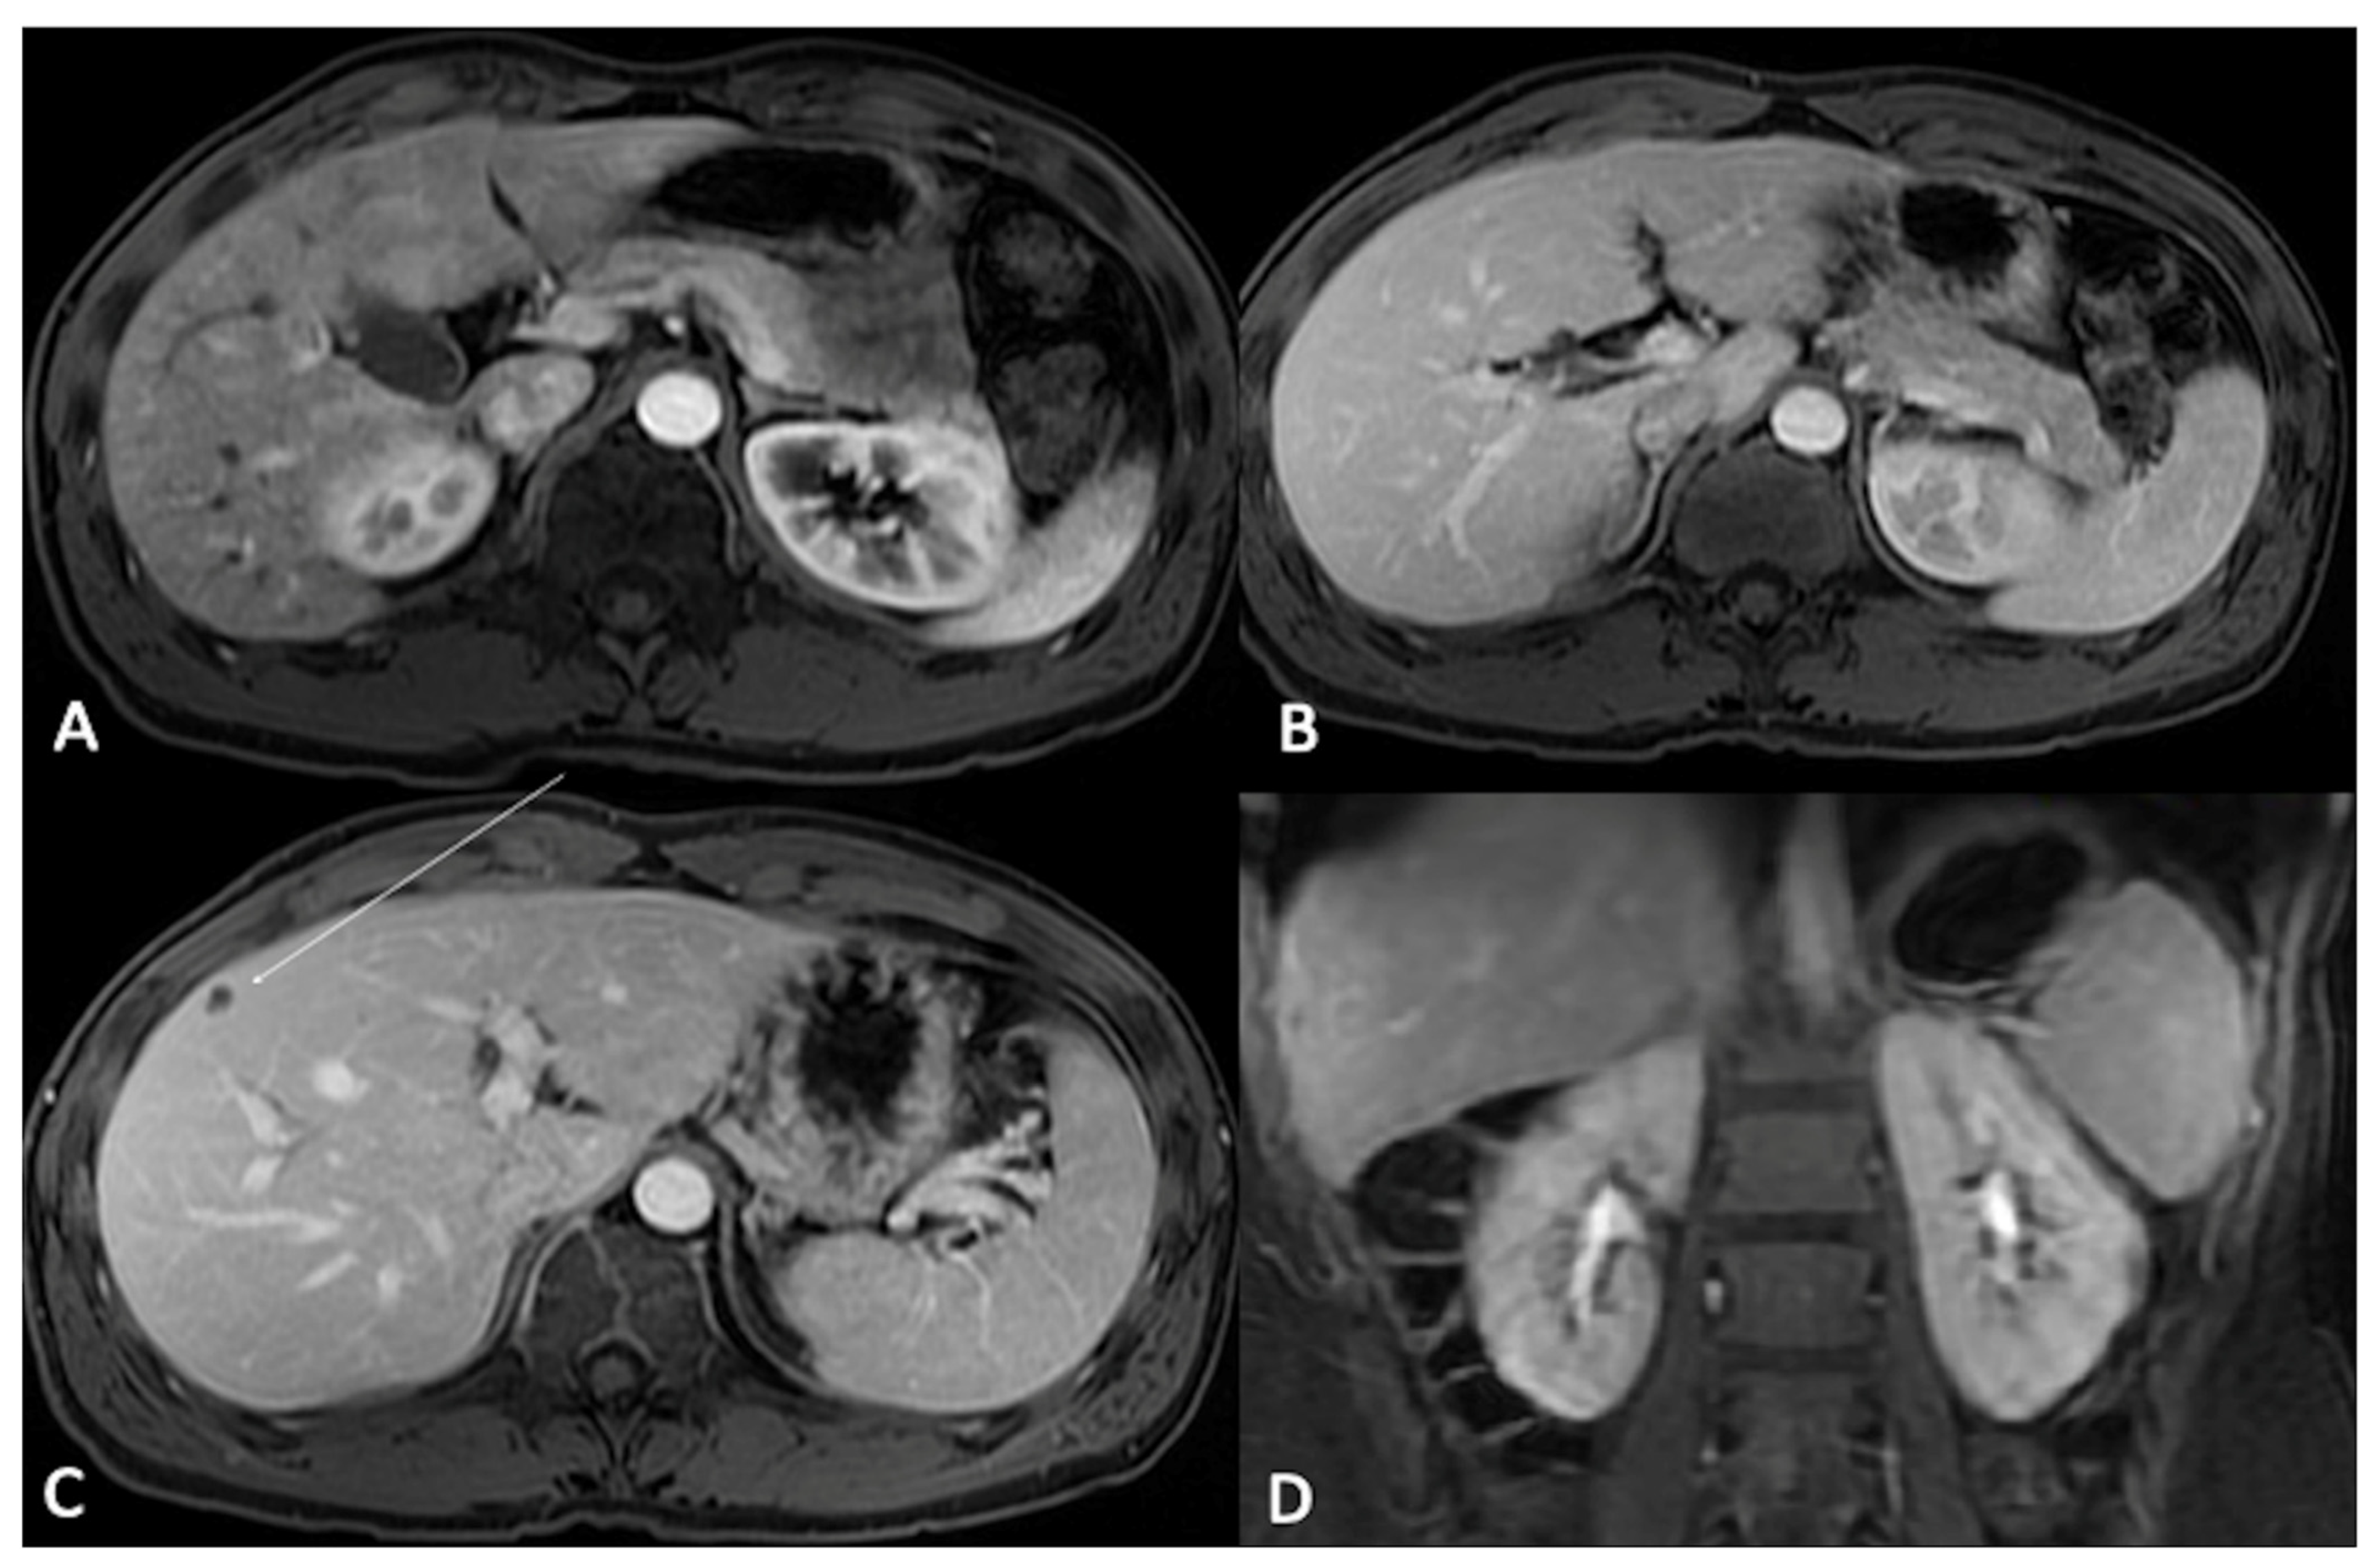

- Hepatocyte-specific contrast agents (HSCAs): Only two molecules are commercially available in this class (gadoxetate disodium and gadobenate dimeglumine); once intravenously injected, they undergo hepatocytes uptake. Their elimination is a combination of biliary and renal clearance (in particular, 50% of godoxetate disodium is excreted in the biliary system, thus with a shorter hepatocellular imaging window occurring approximately 20 min after injection and with a shorter total acquisition time compared to gadobenate dimeglumine of which just 5% is excreted in the biliary system). Due to their properties, HSCAs are mainly used for characterizing focal liver lesions, especially in chronic hepatopathies; off-label indications include bile duct imaging (both pre- or post-surgical or post-traumatic), gallbladder evaluation, and cystic duct obstructions [11,12,13].